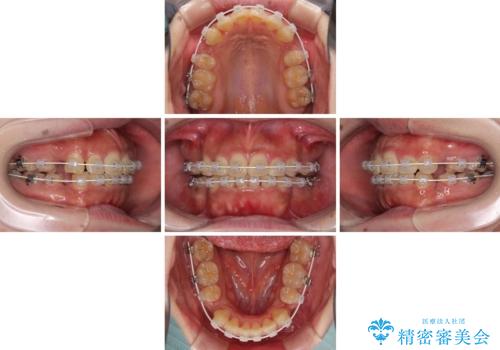

口元の突出感を改善 ワイヤー装置による抜歯矯正

- 口元の突出感と上下前歯のでこぼこを気にして来院された患者様です。

上下前歯部叢生のスペース獲得のため、上下顎左右小臼歯各1歯(計4本)を抜歯して、矯正治療を行うこととしました。

口腔内の清掃性に問題があり、虫歯のリスクが極めて高かったため、短期で治療を終えることを最優先に治療を進めました。